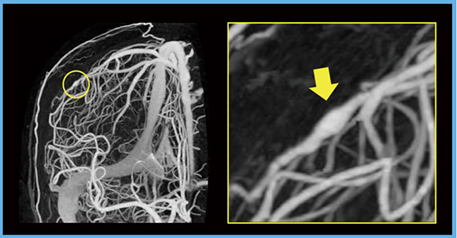

このほか,主幹動脈皮質枝の描出が求められる疾患に感染性動脈瘤がある。感染性動脈瘤の多くは,感染性心内膜炎で心臓弁に付着した疣贅(ゆうぜい:細菌・真菌の塊)が弁から離れ,脳動脈の末梢枝の壁に付着し動脈壁を破壊することで生じ,特に中大脳動脈の末梢枝に多い。致死的合併症を生じるため,早期診断・早期治療が重要である。本動脈瘤は紡錘状の形態を呈するため小さいものは検出しにくく,皮質枝末梢までを描出できるAquilion Precisionは感染性動脈瘤の検出に威力を発揮する(図3)。

図3 感染性動脈瘤